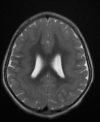

A

Cisto epidermóide

Hipersinal na difusão

Sinal heterogêneo no FLAIR

Extra-axial

19

Q

Cisto epidermóide do SNC

Sinal heterogêneo no FLAIR e Hipersinal na DWI

Extra-axial nas sisternas da base.